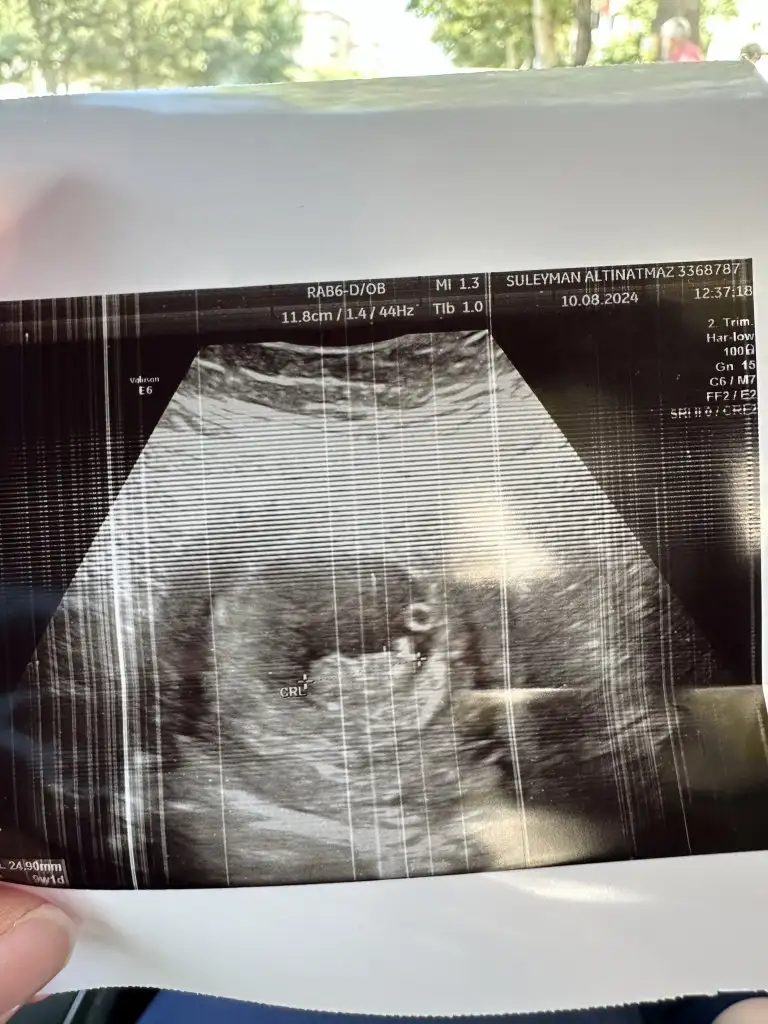

Banada yorum yapar mısın 10+4 olduk.10 gün sonra tekrar gidicem 2li tarama testi için ozaman 12 haftalık olucak ama çok merak ediyorum cinsiyetini 🙃🥰

Eklentiler

• IMG_20240810_223847.webp

IMG_20240810_223847.webp

67,3 KB · Görüntüleme: 72